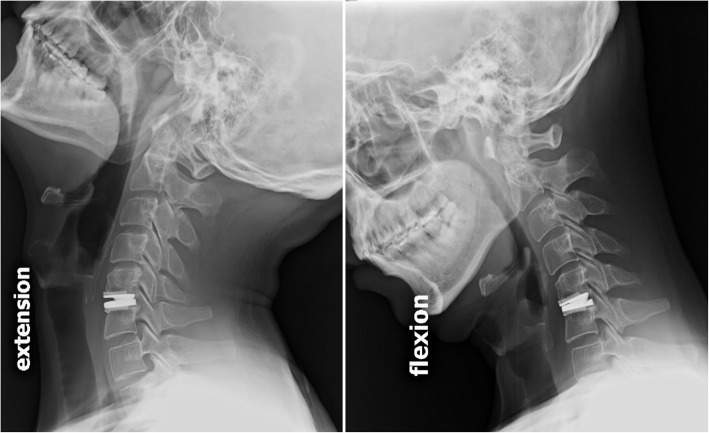

Regular visits at the outpatient department were arranged at pre-operation, and post-operative 6-weeks, and at 3, 6, 12 and 24 months for all patients. Clinical follow-up parameters included visual analog scales (VAS), neck disability index (NDI), and modified Japanese Orthopaedic Association (JOA) scores, which were collected by experienced physician assistants during regular post-operative follow-ups. Routine X-ray images including antero-posterior, lateral, and flexion-extension films were taken at every regular visit at the clinic. Radiological criteria for adjacent segment degeneration (ASD) in X-ray films were the presence of disc space narrowing, osteophytes, or sclerosis of the endplates [25]. Incidences of HO formation were accessed by not only the post-operative lateral radiographs but also by CT scans with three-dimensional reconstruction, and graded according to the McAfee’s classification [26]. Segmental range of motion (ROM) at the index level was determined with standing lateral flexion/extension radiographs (Fig. 1) at post-operative 24-months follow-up using the Cobb method [2, 24]. Radiological measurements were completed by a board-certified neuroradiologist independently using the PACS system software, SmartIris (Taiwan Electronic Data Processing Co., Taiwan).

Fig. 1.

Segmental range of motion (ROM) at the index level on standing lateral flexion/extension X-ray films at post-operative 24-months follow-up from a male patient in the young group (≤40 years old)